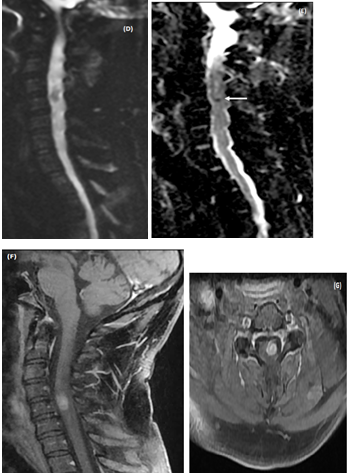

On blood testing at admission the complete blood count, comprehensive metabolic panel, inflammatory markers such as C-reactive protein level were normal. Brain MRI was normal. Spinal cord MRI showed cord enlargement at C4-C5 level and diffuseT2-images high signal from medulla to T4 level. A central area of necrosis hypointense was found on T1-images at C4-C5 level with peripheral enhancement after contrast (Figures 1A-1C). Together, these MRI findings were suggestive of an ISCA. Diffusion weighted images (DWI) showed hyposignal consistent with restricted diffusion on ADC map in the area of the necrotic portion of the cordlesion (Figures 1D&1E).

MRI follow-up at 10 days showed animprovedintramedullary T2 hyperintensity and enhancement, but therewas a residualenhancing nodule at the C4-C5 level (Figures 1F & 1G). At 6months follow-up the neurological examination was unchanged and MRI showed a faint enhancement of the spinal cord at the same level (Figure 1E).

Figure 1 MRI of an intramedullary cervical spinal cord abscess.

(A) T2-weighted sagittal view of the cervical spine shows intramedullary hyper signal intensity from medulla to T4 level together with expansion of the spinal cord, consistent with edema. Note the central area of necrosis at C4-C5 level. T1-weighted sagittal (B) and axial (C) post-contrast images, showring-enhancement of the lesion at C4-C5 level. The vertebral bodies are intact without disc space infection, epidural collection, or sub dural empyema. (D)The enhancing part of the lesionis slighly hyper intense on sagittal Diffusion-weighted (DW)« focus » sequence (E) Restricted diffusion is visible as a dark dot inside the necrotic area on ADC map (arrow). Follow-up MRI of cervical spine (T1-weighted sagittal (F) and axial (G) post-contrast images performed 14 days after initiation of antibiotic treatment shows partial resolution of the lesion. h -At 6 month-MRI follow-up the lesion has disappeared.